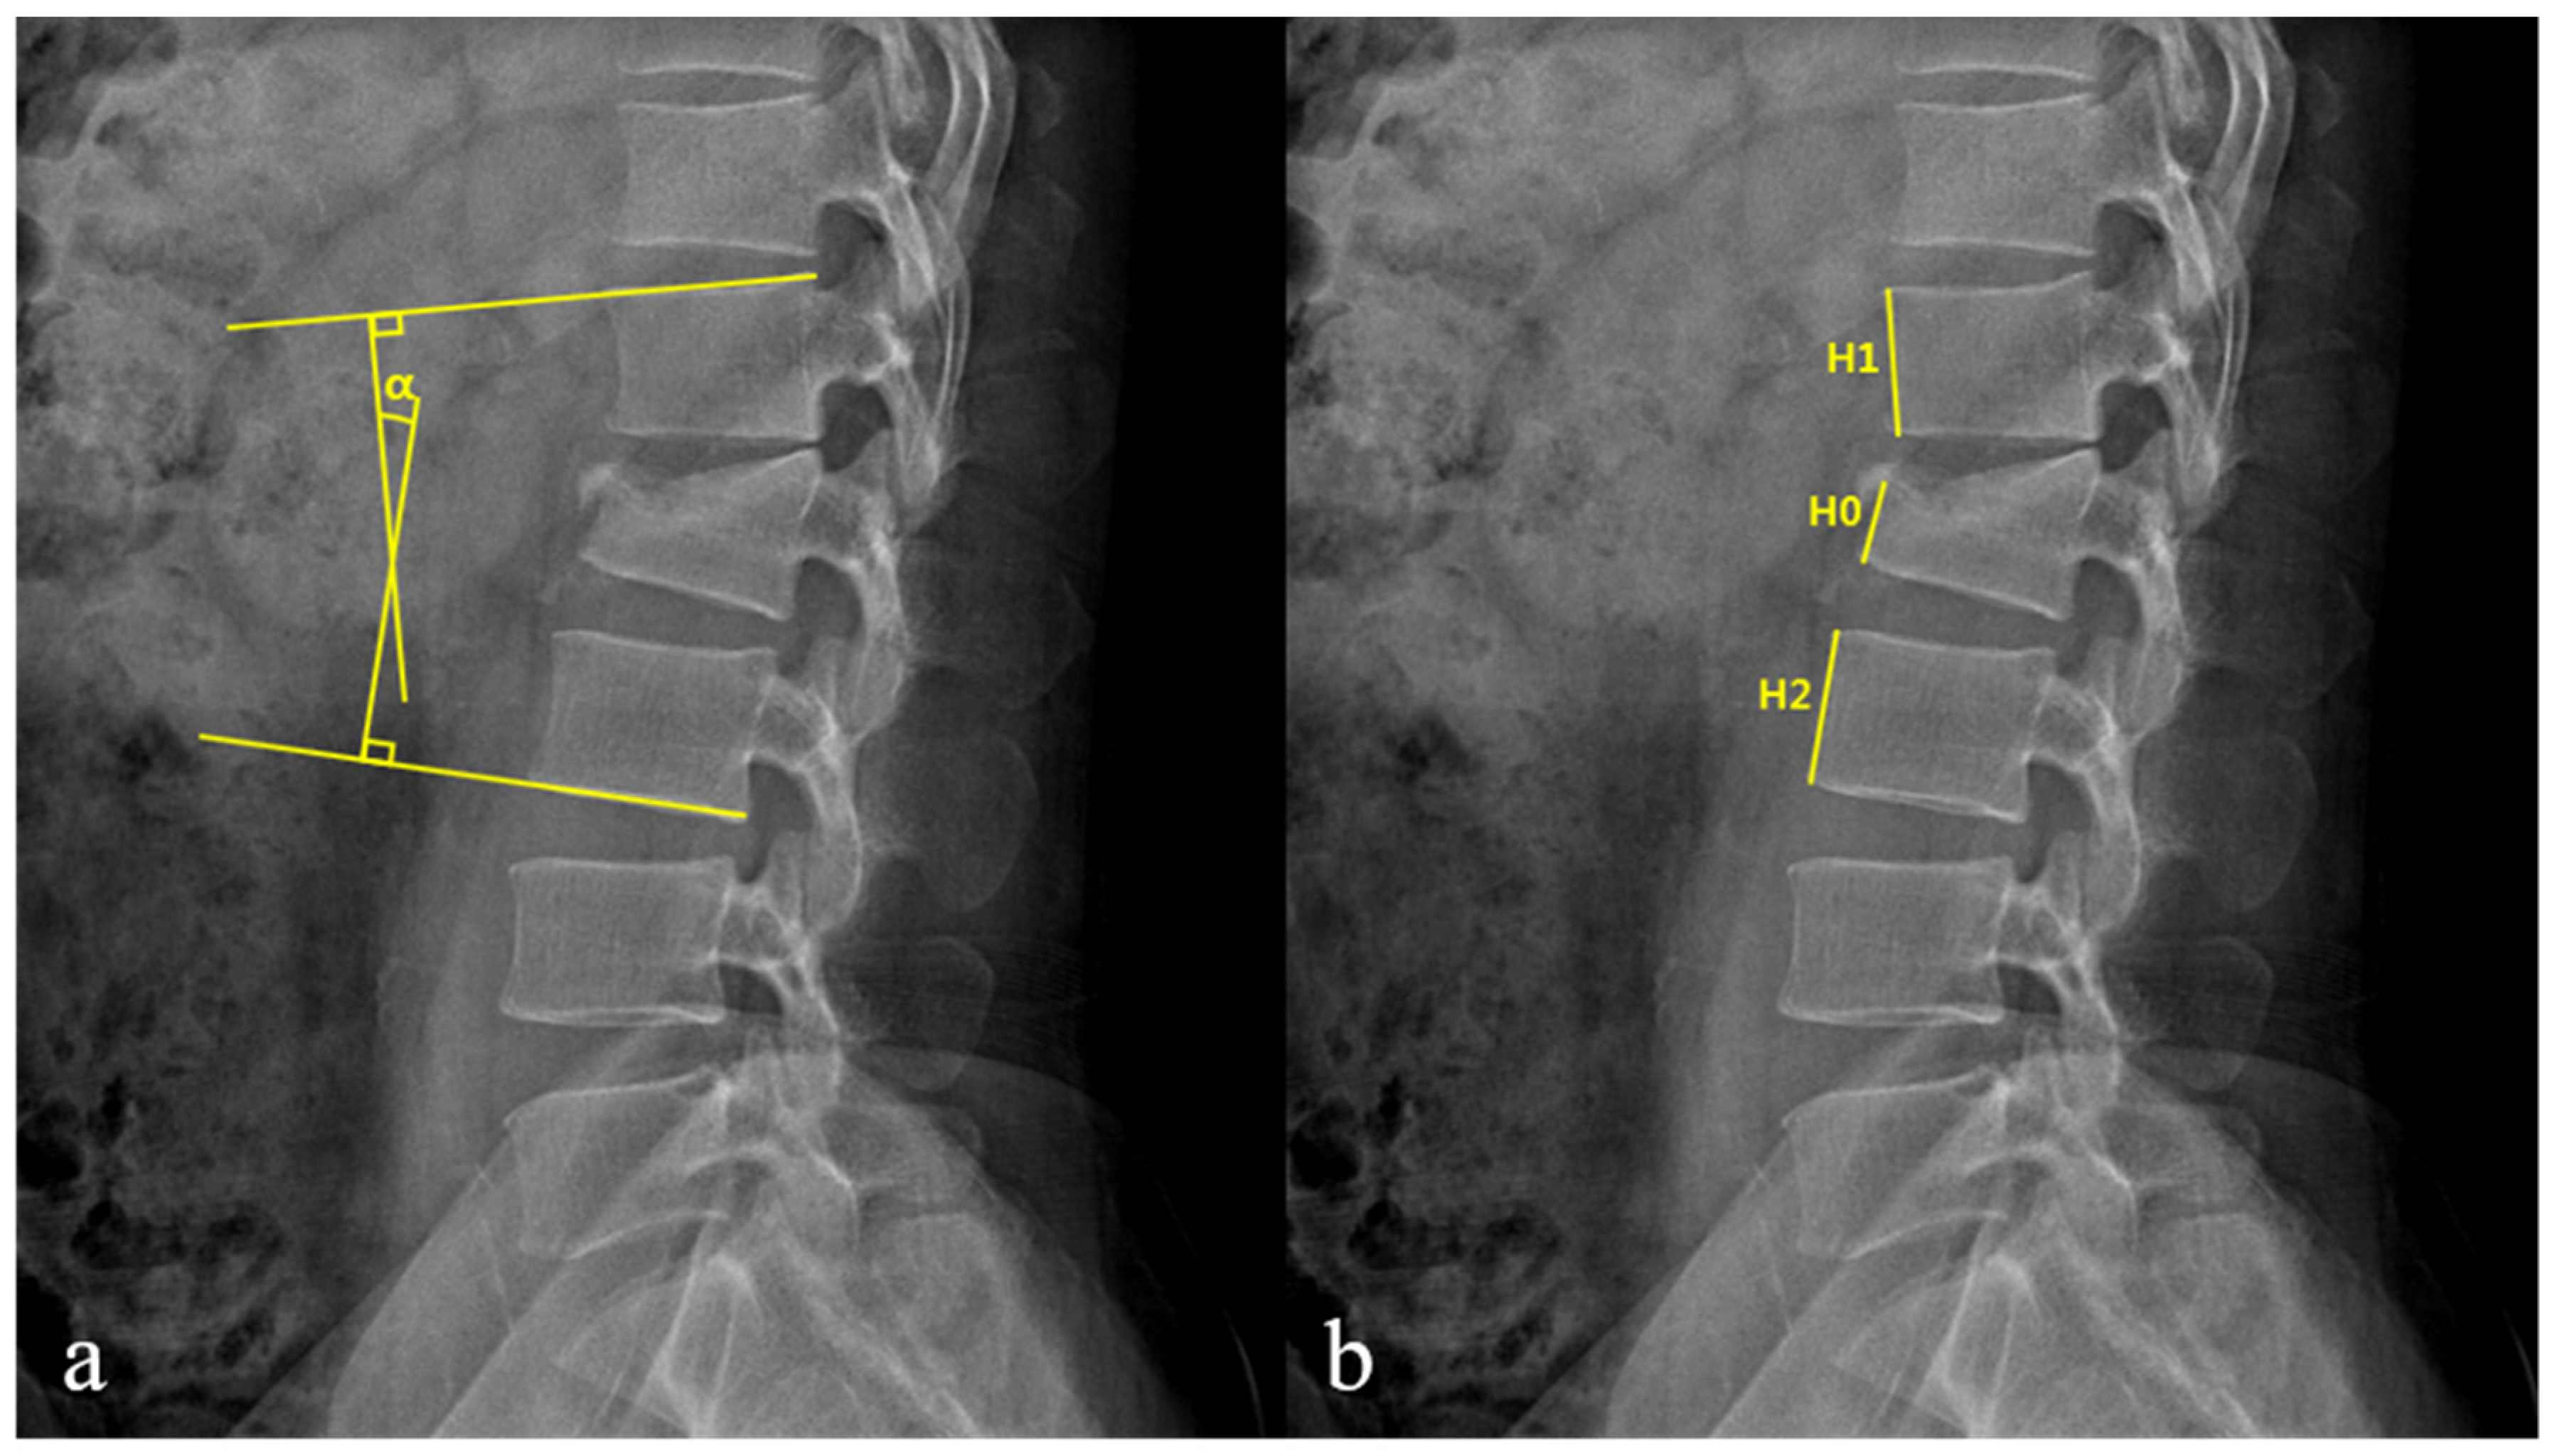

| Spinal canal compromise (%) ‡ | 27.9 ± 7.6 | 35.7 ± 13.3 | 0.03 |

| Loss of vertebral body height (%) ‡ | 28.6 ± 7.8 | 34.1 ± 6.0 | 0.01 |

| Kyphotic angle (°) ‡ | 10.1 ± 6.2 | 13.9 ± 5.0 | 0.04 |